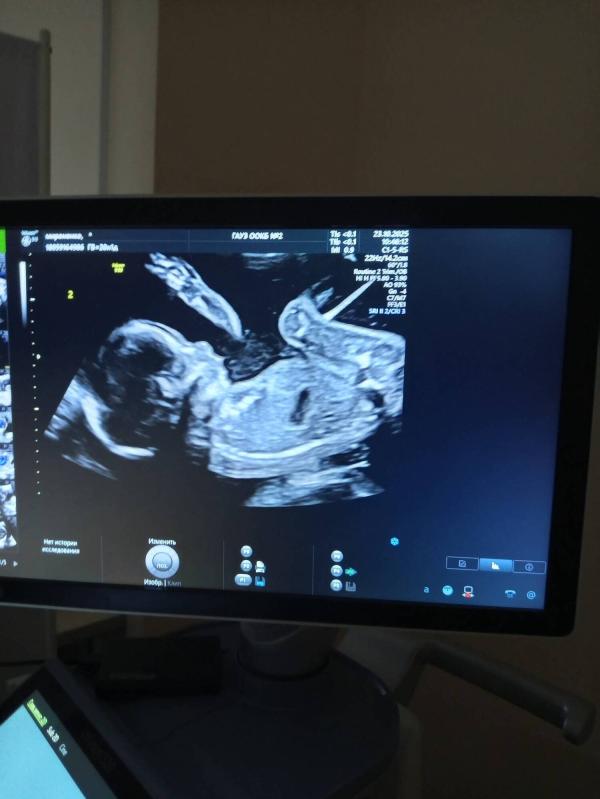

1 - девочка🩷 2 - мальчик💙